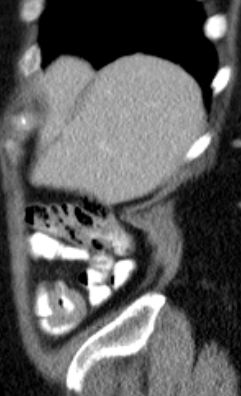

Oft im Gesicht (v.a. Kiefer) oder am Hals. | Innere Organe (v.a. im Bauchraum), im Spätstadium auch ZNS, Knochenmark, Meningen. | ||

Burkitt-Lymphom täuscht einen Dünndarmtumor vor.

Exzision anlässlich einer Rektum-Ca-OP bei einer 80jährigen Frau. | ||||